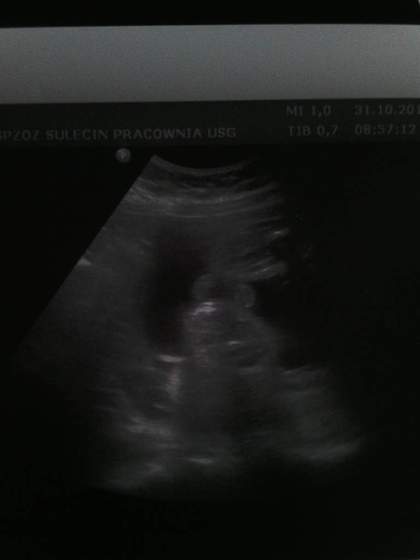

Oficjalnie przedstawiamy Franka :) jest cudny. Rośnie zdrowo i po prostu nie mogłam się na niego napatrzec. Jest idealny :) wazy 1300 g więc zapowiada sie że będzie wagowo jak chłopaki, nie za duży. Na USG fikal jak szalony, aż pani nie mogła się nadziwic. Leży w poprzek i buziaka do zdjęcia za chiny nie chciał wystawić. Pani doktor przelaczala na 3d bo chciała zrobić zdjęcie buziaka i.... jak tylko przelaczala to mały obracał główkę. Ja mualam monitor na ścianie przed sobą więc widziałam go cały czas. Długo byłam bo pani chciała zrobić nam to zdjęcie i...nie dał. Charakterem tatusia :D

• 1414747298494.jpg

1414747298494.jpg

7,8 KB · Wyświetleń: 70